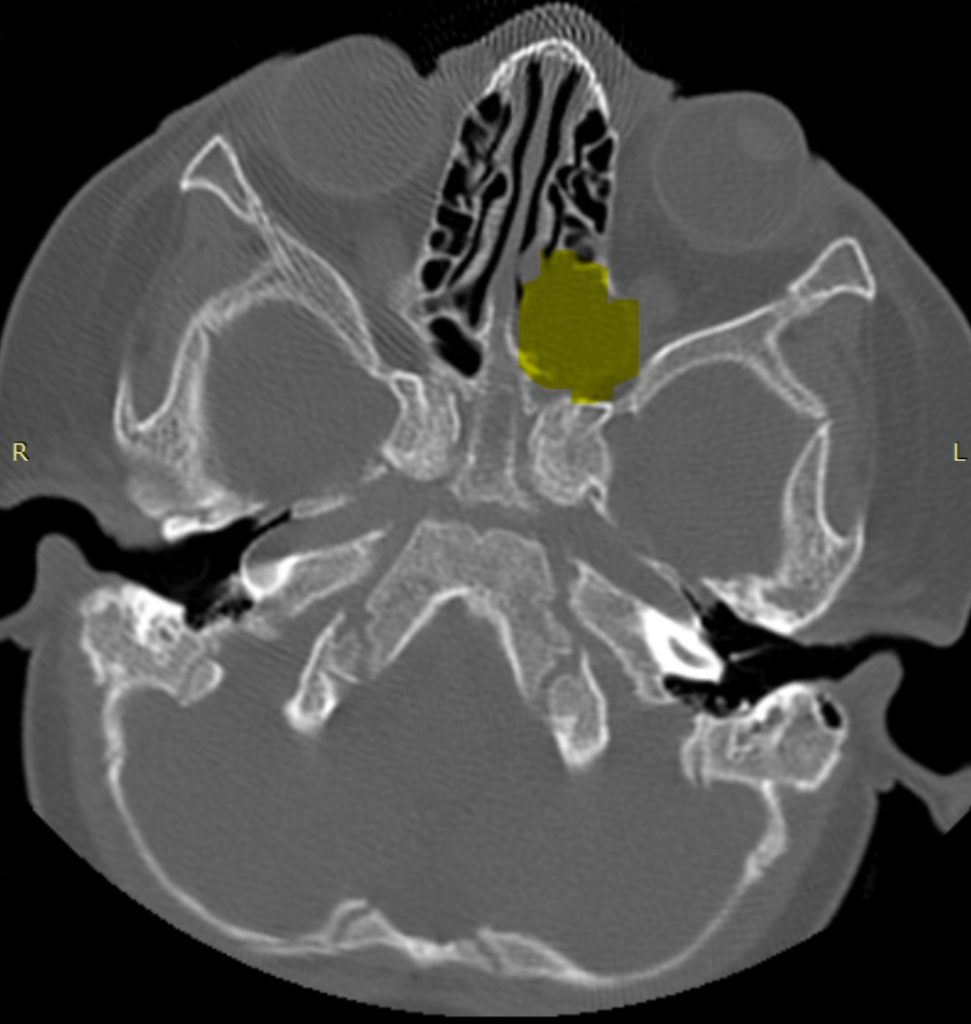

ENDOSCOPIC TRANSNASAL ABLATION OF A LARGE FRONTO-ETHMOIDAL SARCOMA Rezumat: Sarcomul sinonazal bifenotipic este o tumoră rară (149 de cazuri descrise până în prezent în literatura de specialitate)1, ia naștere din mucoasa tractului respirator superior și se caracterizează printr-un comportament biologic agresiv și o tendință accentuată de invazie a bazei craniului și a orbitei. Conform […]

ABLAȚIE ENDOSCOPICĂ TRANSNAZALĂ A UNUI SARCOM FRONTO-ETMOIDAL VOLUMINOS